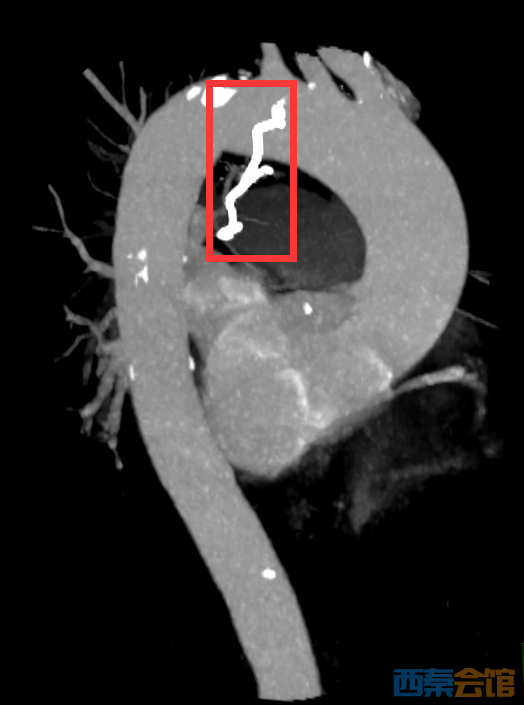

急诊CT显示,异物为假牙的金属钩,已穿透食管壁嵌顿在胸腔内,而且与主动脉弓(人体最大的血管)相隔仅6个毫米,稍有偏差,就有可能被划破引起大出血。情况紧急,且凶险。最好的办法是通过食管镜把异物取出,但风险也高。在做好充分的评估准备保全的预案并与家属充分沟通后,主治医师王茜在全麻下为熊奶奶进行了异物取出手术。